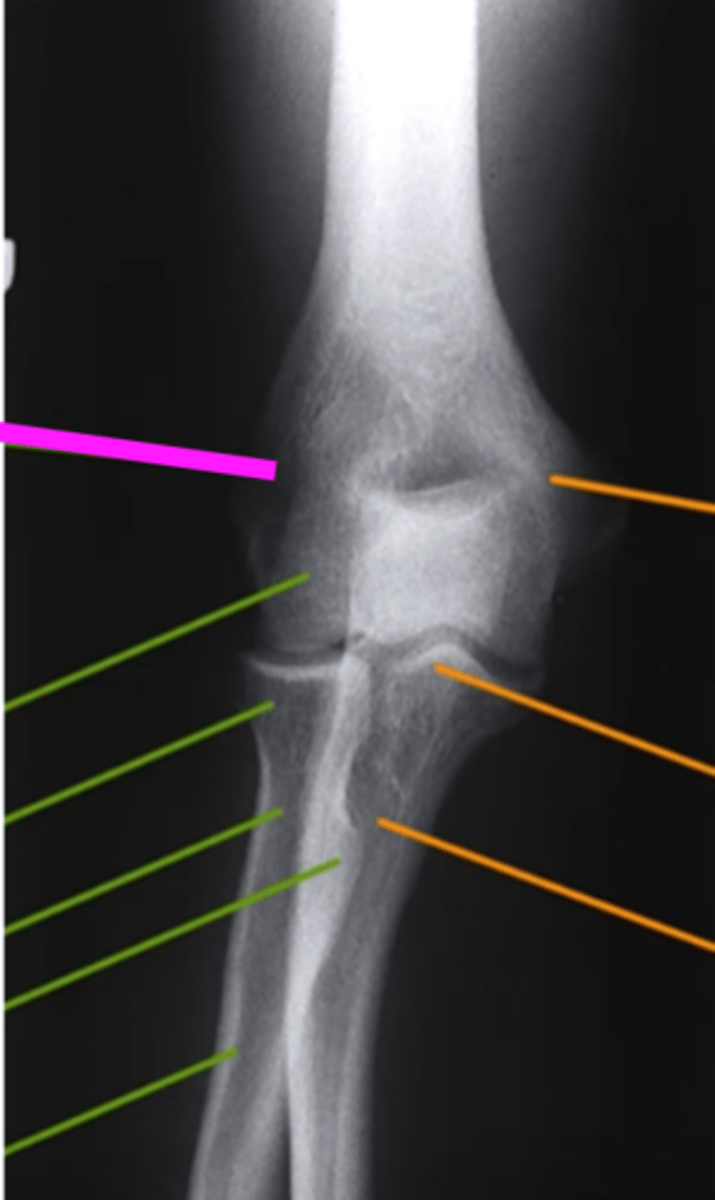

AP Elbow

what view is this

lateral epicondyle

what does the pink line point to?

medial epicondyle

Capitulum

coronoid process

shaft of ulna

shaft of the radius

radial tuberosity

radial head

radial neck